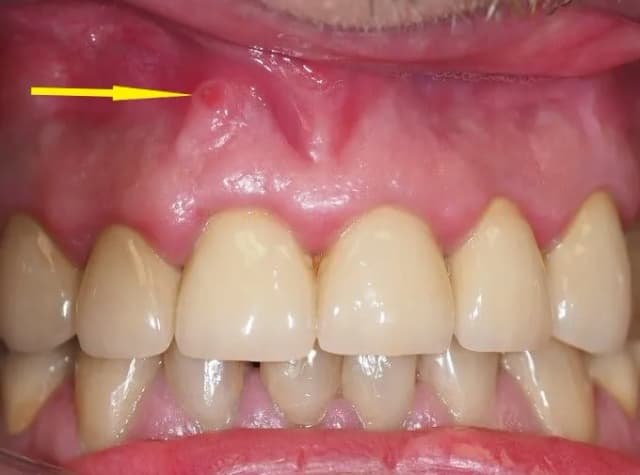

Jak wygląda ropień na dziąśle i jak go skutecznie leczyć

Dowiedz się, jak wygląda ropień na dziąśle, jakie są jego objawy oraz skuteczne metody leczenia, aby szybko przywrócić zdrowie jamy ustnej.